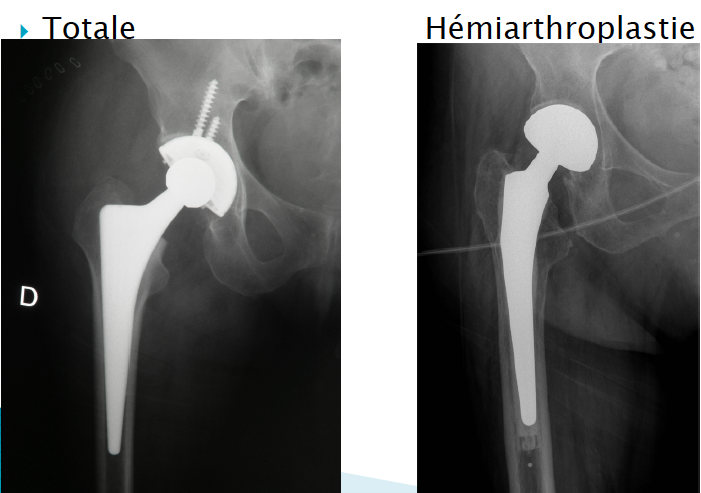

L’arthroplastie totale représente le traitement de choix pour les arthroses de hanches et de genoux. L’avantage de l’arthroplastie est qu’elle permet un soulagement de la douleur articulaire, tout en conservant la mobilité et en préservant la fonction de l’articulation.

Dans les dernières années, la qualité des matériaux s’est nettement améliorée, tant au niveau des prothèses de hanches que de genoux et la durée actuelle moyenne d’une prothèse est d’environ de dix à quinze ans.

**On parle d’hémiarthroplastie si on remplace une seule surface, et d’arthroplastie totale quand on remplace les 2 surfaces en contact. Si on voit des vis, ca veut dire que c’est une arthroplastie totale.

Quelles sont les caractéristiques des prothèse totale de la hanche?

La prothèse totale de la hanche a vu sa popularité exploser dans les dernières années, si bien que le nombre de prothèses totales de hanches a plus que doublé au cours des dix dernières années, tant aux États-Unis qu’au Canada.

Les principaux couples de friction dans une prothèse de hanche sont une surface métallique sur une surface de polyéthylène. Ceci représente le couple de frottement standard depuis l’apparition des prothèses de hanches dans les années 1970. Par contre, des nouveaux procédés ont été développés avec la possibilité d’implanter des articulations métal-métal ou en céramique. Les études démontrent la présence d’une survie articulaire d’environ 90 à 95 %, à quinze ans, pour les types de prothèses de hanches utilisées de nos jours.